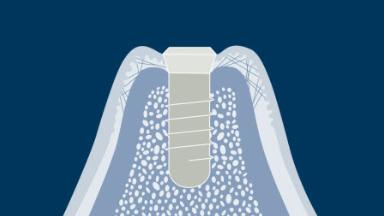

Este módulo concentra-se no conceito de integração de implantes dentários nos tecidos moles e duros da cavidade oral. A integração no osso é chamada de osseointegração e esse fenômeno, em específico, revolucionou essencialmente a maneira como os dentes ausentes podem ser substituídos. A osseointegração tem implicações clínicas para todas especialidades de dentistas envolvidas, bem como para pacientes com qualquer ausência de elementos dentários. Implantes são ancorados no tecido ósseo e penetram no tecido mole. É essencial entender os tecidos moles e duros ao redor de reabilitações sobre implantes dentários, pois somente isso permite reabilitações ideais.

- discutir como ocorre a integração dos tecidos ósseos ou a osseointegração

- discutir como ocorre a integração dos tecidos moles e diferenciá-la com a de dentes naturais